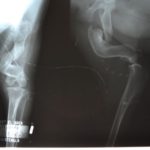

Sweet mama Kesha was likely struck by a car. Her left hind leg was very badly fractured, and she was pregnant. As she was living on her own on the street, there was no one to help her. She gave birth to nine puppies under an abandoned car in the town of San Juan del Obispo. It was cold, and she couldn’t move very well because of her terrible fracture. Four of her puppies died in the cold, unable to locate her and to keep warm.

Unfortunately, the damage to Kesha’s femur and surrounding tissue was so great that we had to have her leg amputated. Because it was such a difficult amputation, our vet elected to spay her at a later date.